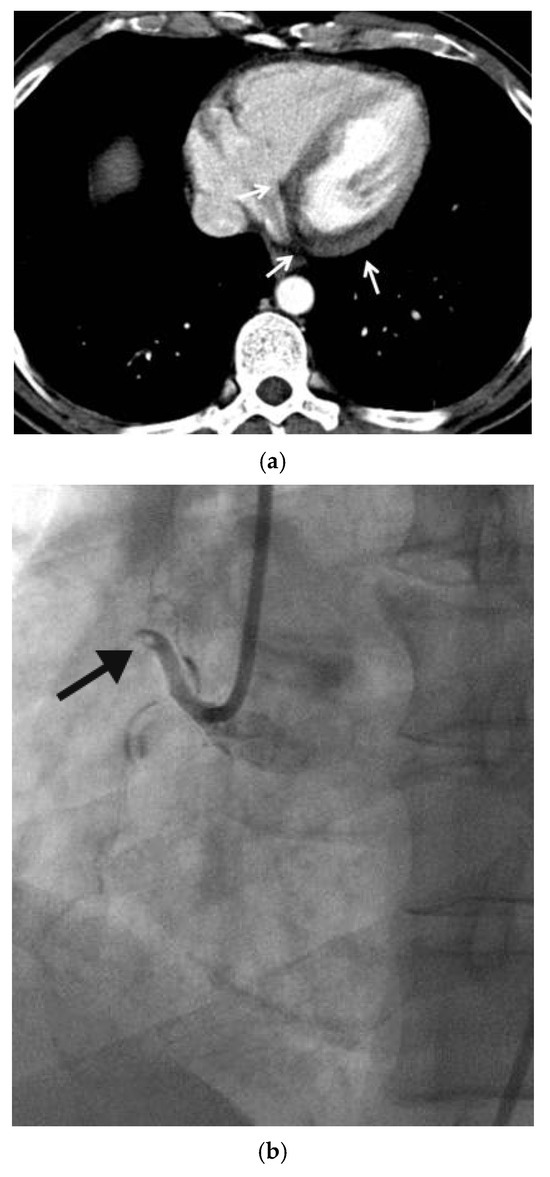

The Middle Meningeal Artery (MMA) occupies a pivotal role in the pathophysiology of migraine, functioning as a vascular and neuroimmune interface that precipitates the characteristic pulsatile pain. The inhibition of this pathophysiological cascade has been investigated as a therapeutic strategy. However, fewer than a dozen centers globally have disseminated procedural or mechanistic data. Given the nascency of this field and the imperative for standardization, the present review synthesizes mechanistic and clinical evidence underpinning intra-arterial pharmacological modulation of the MMA for migraine management. Methods: A focused narrative review was undertaken, drawing upon select but influential studies from pioneering research groups investigating intra-arterial interventions targeting the MMA. The extant literature was thematically categorized and organized according to the loci of cascade interruption and their corresponding clinical outcomes. Results: Since 2009, intra-arterial therapies for severe headache syndromes have evolved, initially utilizing nimodipine for vasospasm-related headaches, progressing to verapamil for reversible cerebral vasoconstriction, and more recently, lidocaine for refractory or status migrainosus, occasionally in conjunction with MMA embolization. Contemporary research uses language that conceptualizes migraine as an immunologically mediated neurovascular disorder, as opposed to a purely vascular or neuronal entity. Recent investigations have identified interleukins such as Interleukin-1β, Tumor Necrosis Factor-α, and Interleukin-6 as critical amplifiers of trigeminovascular activation. Purinergic signaling through the P2X3 receptor and the P2Y13 receptor, in conjunction with pituitary adenylate cyclase-activating polypeptide and vasoactive intestinal peptide pathways, has been implicated in the modulation of MMA excitability and neuropeptide release. The development of novel calcitonin gene-related peptide receptor antagonists, such as zavegepant, further substantiates the artery’s significance as a pharmacological target. Conclusions: These findings support a shift toward immune-modulating intra-arterial therapeutic strategies, with migraine interventions targeting cytokine and neuroimmune signaling within the MMA, rather than relying exclusively on vasodilatory mechanisms.